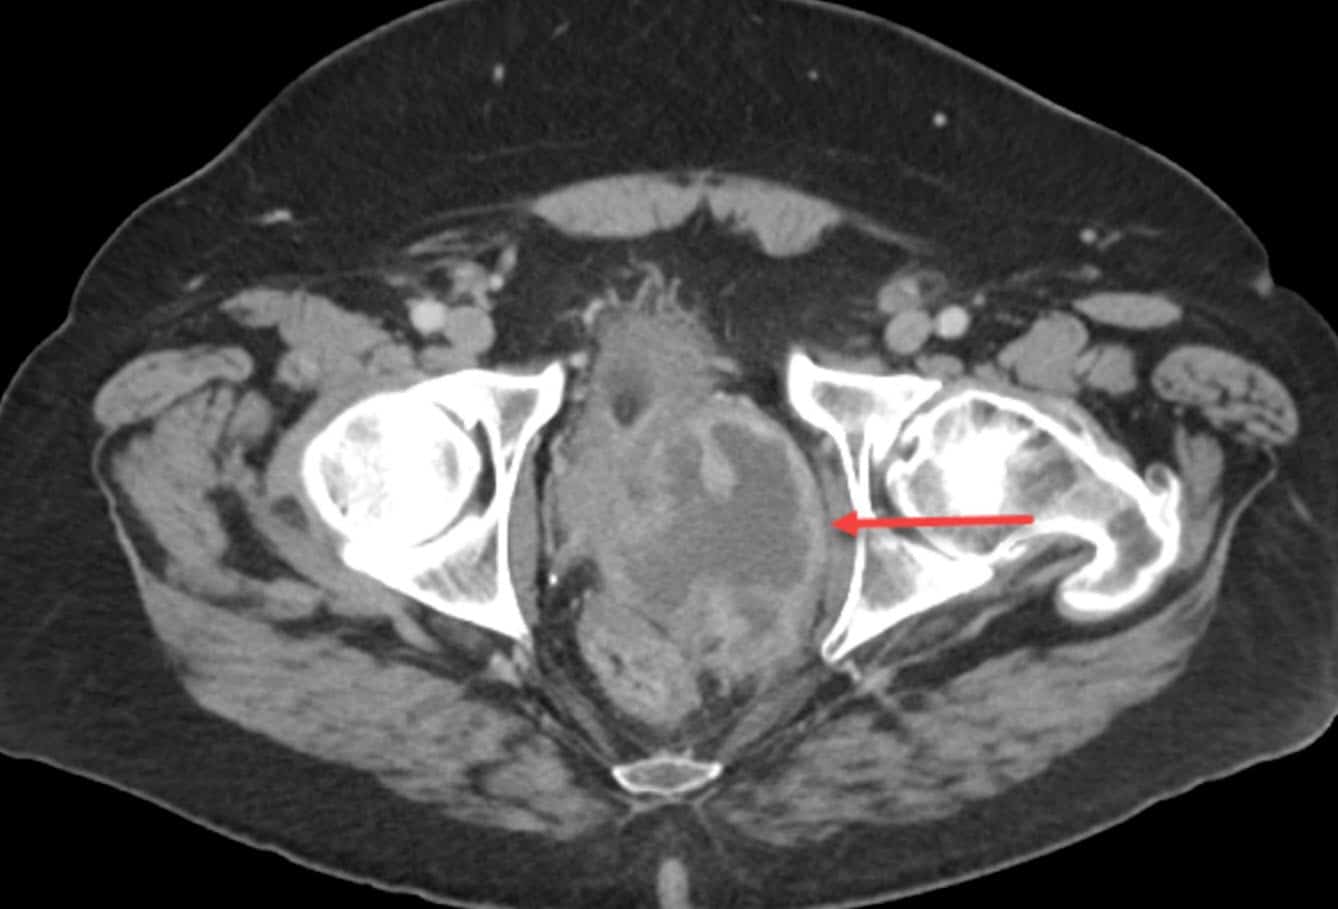

Diagnostic tests benign prostatic hyperplasia (bph) several tests help to confirm benign prostatic hyperplasia (bph) diagnosis:

Diagnostic tests benign prostatic hyperplasia (bph) several tests help to confirm benign prostatic hyperplasia (bph) diagnosis:

Diagnostic tests benign prostatic hyperplasia (bph) several tests help to confirm benign prostatic hyperplasia (bph) diagnosis:

Diagnostic tests benign prostatic hyperplasia (bph) several tests help to confirm benign prostatic hyperplasia (bph) diagnosis:

Diagnostic tests benign prostatic hyperplasia (bph) several tests help to confirm benign prostatic hyperplasia (bph) diagnosis:

Diagnostic tests benign prostatic hyperplasia (bph) several tests help to confirm benign prostatic hyperplasia (bph) diagnosis:

Diagnostic tests benign prostatic hyperplasia (bph) several tests help to confirm benign prostatic hyperplasia (bph) diagnosis:

Diagnostic tests benign prostatic hyperplasia (bph) several tests help to confirm benign prostatic hyperplasia (bph) diagnosis:

Diagnostic tests benign prostatic hyperplasia (bph) several tests help to confirm benign prostatic hyperplasia (bph) diagnosis:

Diagnostic tests benign prostatic hyperplasia (bph) several tests help to confirm benign prostatic hyperplasia (bph) diagnosis:

Diagnostic tests benign prostatic hyperplasia (bph) several tests help to confirm benign prostatic hyperplasia (bph) diagnosis: